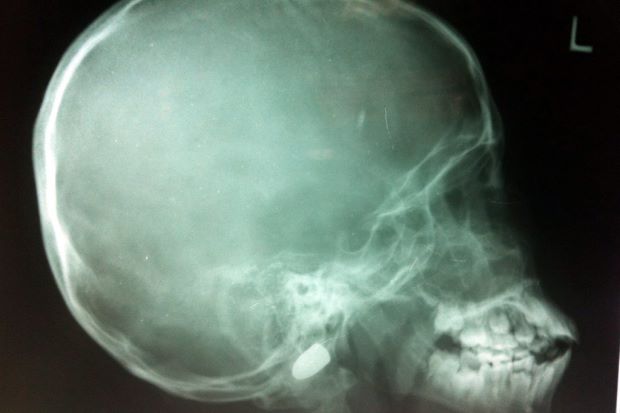

Specialists still undecided on approach to remove bullet from boy’s head

IPOH: Specialists at the Raja Permaisuri Bainun Hospital here will need few more days to decide on the best approach to remove the bullet from Mohd Amar Mohd Azizi’s head.

Hospital director Dr Raja Lope Ahmad Raja Ariffin said on Friday the doctors were still discussing on the safest procedures with minimal risk on the boy.

It was reported that Mohd Amar, 10, was hit by a stray bullet when an off-duty police officer discharged his pistol when cleaning it at Kampung Belanja Kiri in Parit on Monday.

The bullet was lodged on the joint between the skull and neck bone, just 1cm away from his spinal cord and arteries.

The hospital’s neurosurgeon Dr Cheang Chee Keong was reported saying that he wished the surgery could be carried out latest by today (Oct 18), as he feared movements in the bullet might damage the spinal cord and arteries.